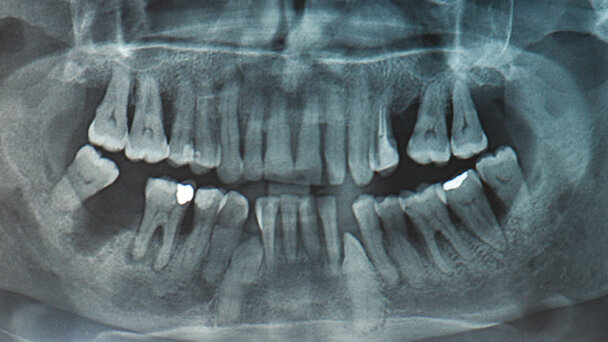

La paziente donna 64 anni si presenta all’attenzione del dentista con un quadro clinico generale complesso. Eseguita l’anamnesi si procede a un’ispezione del cavo orale che accerta come la stabilità di tutti i denti è gravemente compromessa a causa di una parodontosi in stadio avanzato e alla presenza di canini inclusi come si evince anche dalla radiografia iniziale (Fig. 1).